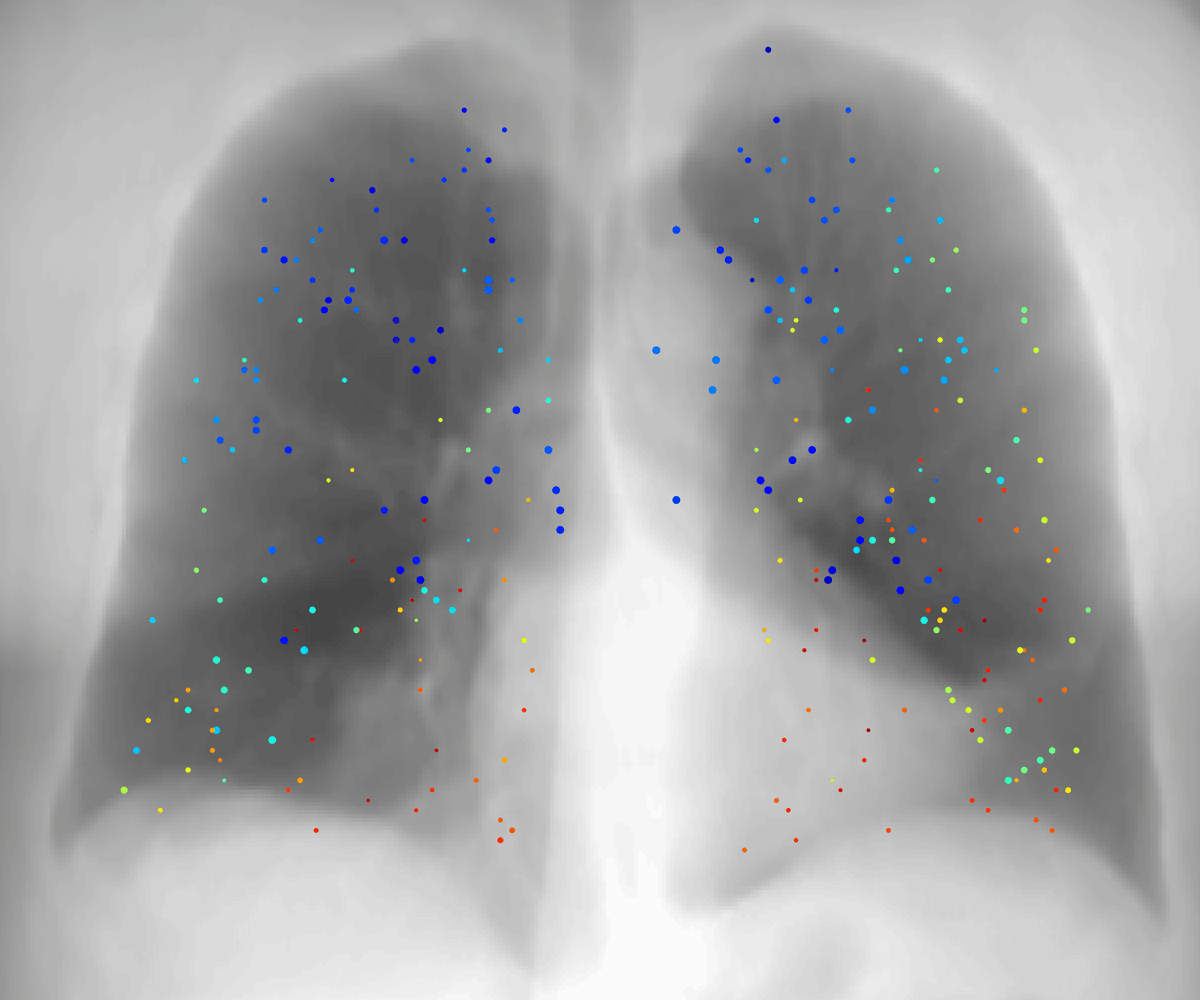

CPT-4DMR: Continuous 4D-MRI

A continuous function representation f(x, y, z, t) for 4D-MRI that eliminates binning artifacts and enables high-quality volumetric MRI reconstruction at arbitrary respiratory phases, critical for tracking irregular breathing motion.

CPT-4DMR: Continuous sPatial-Temporal representation for 4D-MRI reconstruction

Xinyang Wu*, Muheng Li*, Xia Li*, Orso Pusterla, Sairos Safai, Philippe C. Cattin, Antony Lomax, Ye Zhang

Preprint, 2025

Proposes a continuous spatio-temporal representation f(x, y, z, t) for 4D-MRI, enabling reconstruction at arbitrary respiratory phases and reducing binning artifacts.